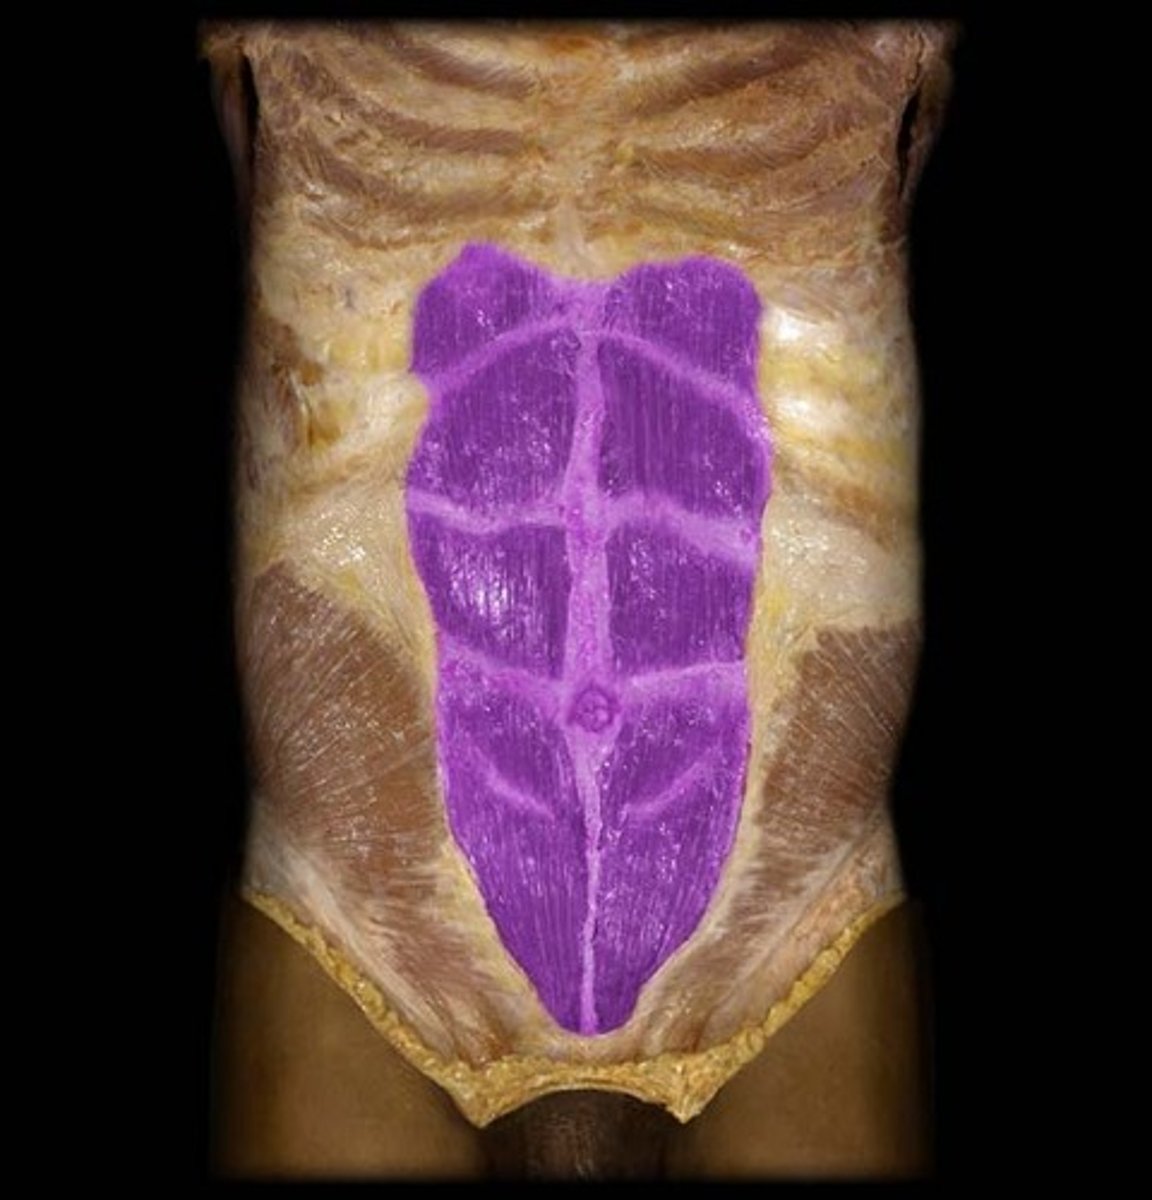

Rectus Abdominus

Origin: Pubic symphysis and superior margin of pubis

Insertion: Xiphoid process; costal cartilages 5-7

Action: flexes trunk, stabilizes pelvic region during walking, and compresses abdominal viscera

Linea Alba

Non-muscular, fiberous structure running between xiphoid process and pubic symphysis

Insertion: site for transverse abdominis